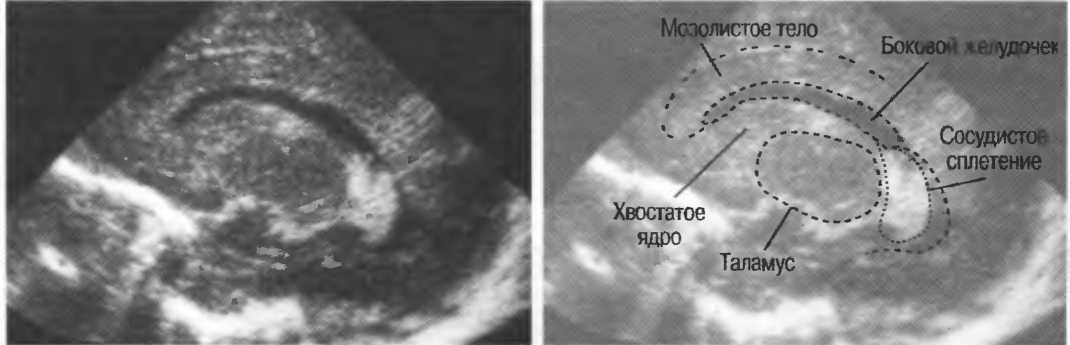

3. Ультразвуковые исследования в педиатрии. Для детей необходим датчик с частотой 5 МГц с глубиной фокусировки на 5-7 см. При исследовании мозга новорожденного используется секторный датчик с частотой 7,5 МГц с глубиной фокусировки на 4-5 см (этот датчик также используется для исследования яичек и структур шеи у взрослых).